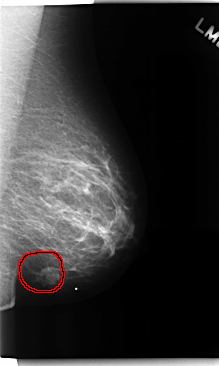

C_0161_1.LEFT_MLO

LEFT_MLO LINES 4752 PIXELS_PER_LINE 2840 BITS_PER_PIXEL 12 RESOLUTION 50 OVERLAY

FILE: C_0161_1.LEFT_MLO.OVERLAY

TOTAL_ABNORMALITIES 1

ABNORMALITY 1

LESION_TYPE MASS SHAPE LOBULATED MARGINS MICROLOBULATED

ASSESSMENT 5

SUBTLETY 5

PATHOLOGY MALIGNANT

TOTAL_OUTLINES 1

BOUNDARY